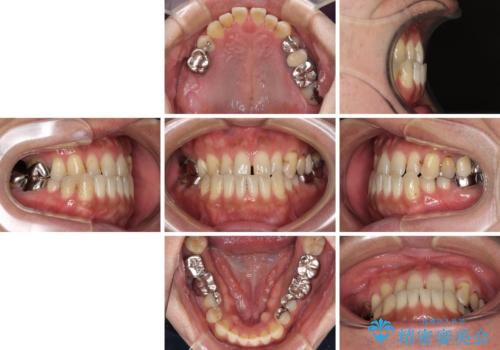

- 咬み合わせの悪さを気にして来院された患者様です。

来院当初は、奥歯の銀歯が問題で咬み合わせが悪いと思っていらっしゃいましたが、前歯の反対咬合を改善することが最優先とご説明し、矯正治療を行うこととしました。

奥歯には抜歯が必要な歯があったため、事前に抜歯を行い、その後ワイヤー装置にて治療を開始しました。

前歯の反対咬合が改善する過程では、奥歯が咬みにくくなるため、食事では辛い思いをされていたようです。

矯正治療後は安定した咬み合わせとなり、顎の違和感がなくなったとのことでした。